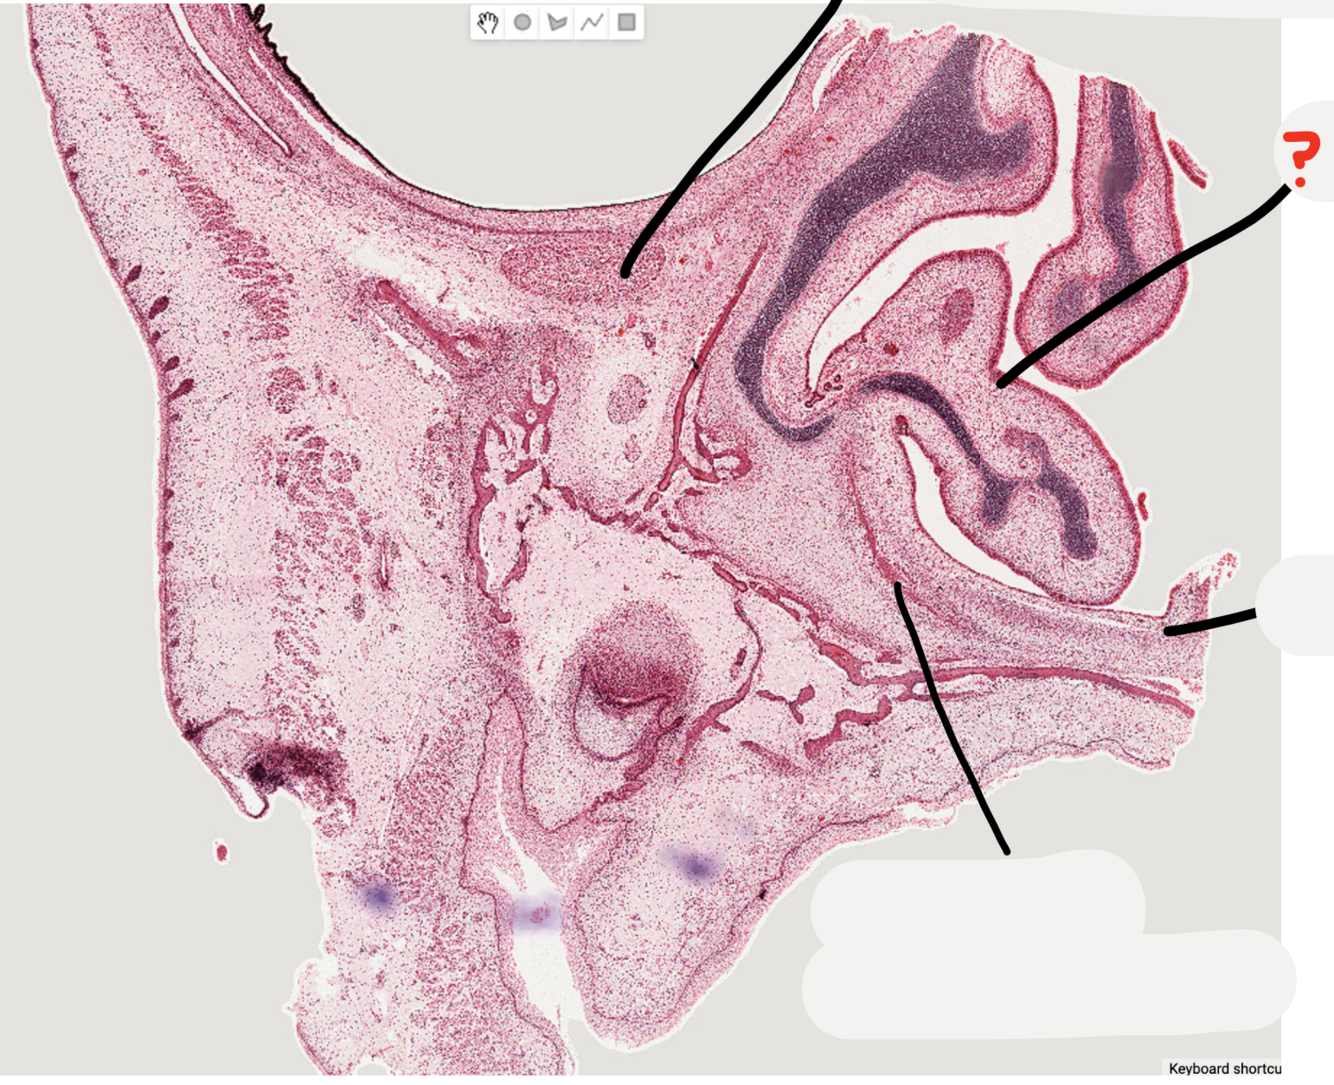

9

Q

A

infraorbital nerve

10

inferior nasal concha

11

palatal process of developing maxillary bone

12

alveolus of developing maxillary bone

13

enamel organ

14

dental follicle

15

dental papilla

16

successional lamina

17

dental lamina

18

vestibular lamina